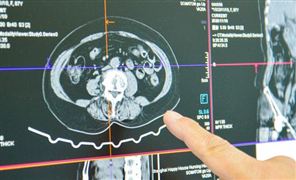

医学影像是指为了医疗或医学研究,对人体或人体某部分,以非侵入方式取得内部组织影像的技术与处理过程。它包含以下两个相对独立的研究方向:医学成像系统(medical imaging system)和医学图像处理(medical image processing)。前者是指图像行成的过程,包括对成像机理、成像设备、成像系统分析等问题的研究;后者是指对已经获得的图像作进一步的处理,其目的是或者是使原来不够清晰的图像复原,或者是为了突出图像中的某些特征信息,或者是对图像做模式分类等等。